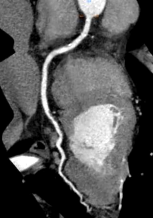

Công nghệ tim mạch Aheart

Phương pháp chỉnh sửa ECG

Hình ảnh lâm sàng